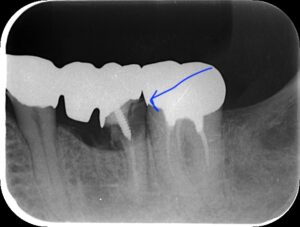

コーヌスデンチャーとは残っている歯に冠のような金属を被せてその上にさらに金属を被せる

2重の冠でできた入れ歯になります。茶筒の原理で固定されるため安定感が高く、審美性や装着感に

優れています。ドイツで開発されたテレスコープデンチャーの一種です。